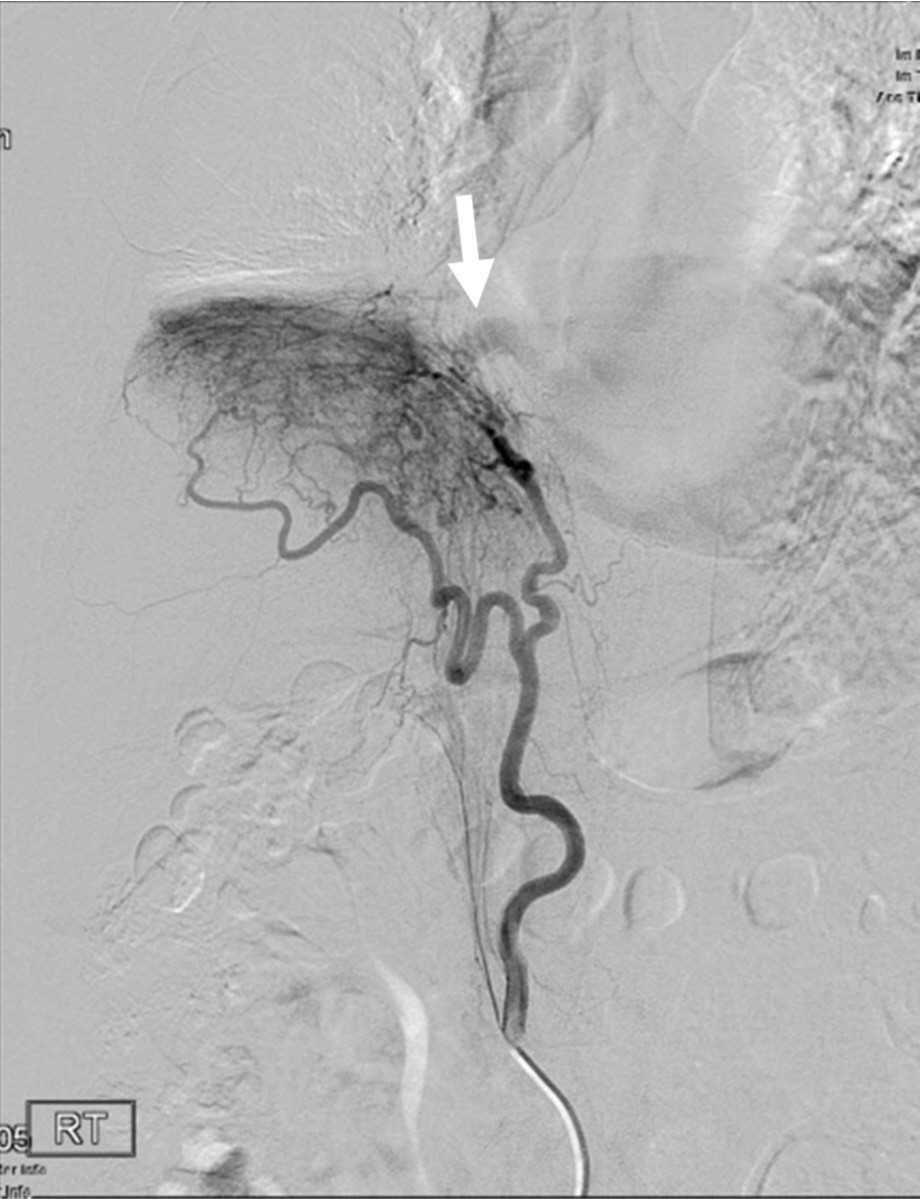

Fig. 4.

Fig. 4. Selective angiogram of the right inferior phrenic artery shows arterial hypertrophy, hypervascular parenchymal staining in the right lower lung field, and shunting to pulmonary circulation (arrow).